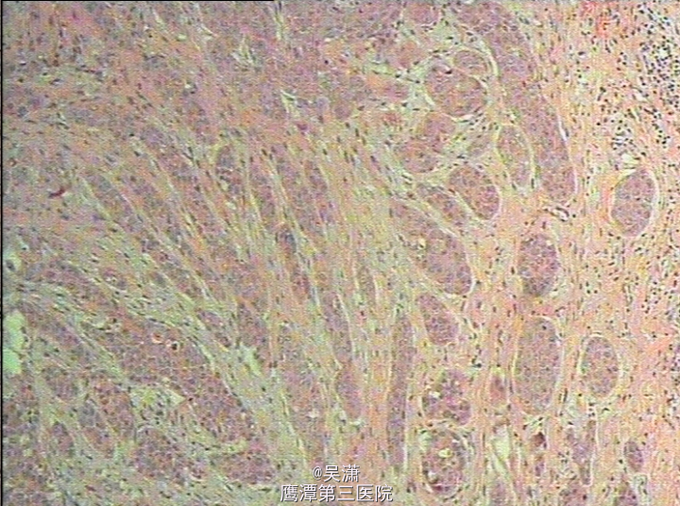

查体:左侧颞枕部可见一8cm*4cm大小类圆形陈旧性暗红色移植后皮片。上可见3个约0.5cm*0.5cm大小的术口,并少许渗血、渗液。 辅助检查:2014-03-11我院病理结果示:(头皮肿物)高分化鳞癌。2014-04-29我院术后病理示:镜下见部分组织被覆鳞状上皮,未见确切癌组织残留。2014-12-31我科病理检查提示:符合鳞状细胞癌复发。血常规 淋巴细胞绝对值3.480x10E9/L;生化十一项:高敏C反应蛋白4.420mg/L。头部CT检查结果示:肿瘤侵犯少许颅骨外板。

诊断:头皮鳞状细胞癌复发 处理:全麻下行莫氏纤维描记手术方式扩大切除头皮恶性肿瘤+皮瓣成形+腹部取皮+植皮术+部分颅骨切除+修复术。 术后24小时予头孢曲松钠(罗氏芬)2g ivdrip预防感染,定期伤口换药。